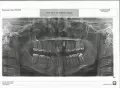

Проконсультируйте, пожалуйста, не высоко ли установлен имплант? В моей клинике считают, что правильно, но вопрос в том, что не хватает десны для установки коронки, почему возникла такая проблема? Можно это было предотвратить или предусмотреть? И что можно сделать, чтобы исправить ситуацию?

Планирование хирургического и ортопедического этапа лечения перед операцией гарантирует успешный конечный результат. В вашем случае имплантат стоит немного, неудобно для протезирования. И все-таки при грамотном подходе дефект можно максимально минимизировать. Обратитесь к опытному стоматологу-ортопеду или приезжайте ко мне, я постараюсь вам помочь.